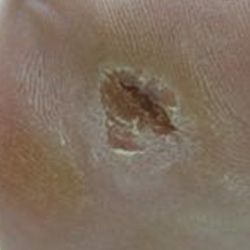

Before and After

Electrical Burn Injury